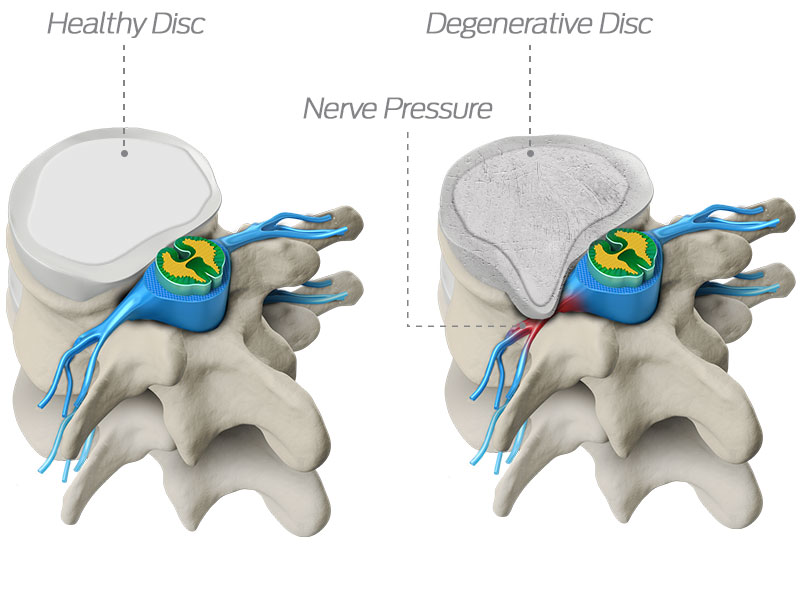

#Spinaldisc pathology can cause leg and/or #backpain -if you're suffering call us for a consultation 0207 935 4750

Do you suffer from sharp pains every time you bend? Back pain, of this nature, is often the result of a #herniateddisc or #pinchednerve: both caused by preventable #spinaldisc problems. Before considering drugs/surgery, a chiropractor can help! Book your appointment today!

As we age, our spinal discs degenerate, which may cause the disc to lose its height or bulge out—potentially compressing a nerve, causing pain or other symptoms. Learn more about spinal discs at rediscovermylife.org/anatomy.php. #rediscover #centinelspine #spinaldisc #discbulge

Treating A Degenerated Spinal Disc Symptoms of degenerative disc disease include pain, paresthesia, and weakness. Spinal fusion surgery is used when symptoms worsen. #spinaldisc #degeneration #mvscburnsville zurl.co/hr68

#Spinaldisc pathology can cause leg and/or #backpain -if you're suffering call us for a consultation 0207 935 4750

Do you suffer from sharp pains every time you bend? Back pain, of this nature, is often the result of a #herniateddisc or #pinchednerve: both caused by preventable #spinaldisc problems. Before considering drugs/surgery, a chiropractor can help! Book your appointment today!